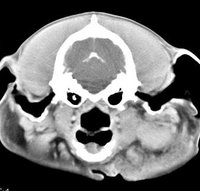

imágenes de TC en el perro | ||||||||||

ejemplo de imágenes de TC en el perro. Nótese la celulitis en la región parotídea izquierda | ||||||||||